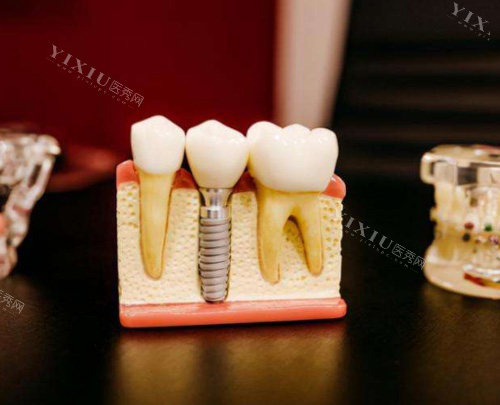

韩国进口种植牙:4980元起/颗(含种植体+基台+牙冠)

此外,院内不定期推出优惠活动,如种植牙集采价低至4980元/颗,进一步降低患者经济负担。

“选择韩国进口种植牙,总费用4980元。医生技术正规,术后无不适,改善结果满意。还赠送了一年的免费维护服务,非常贴心。”